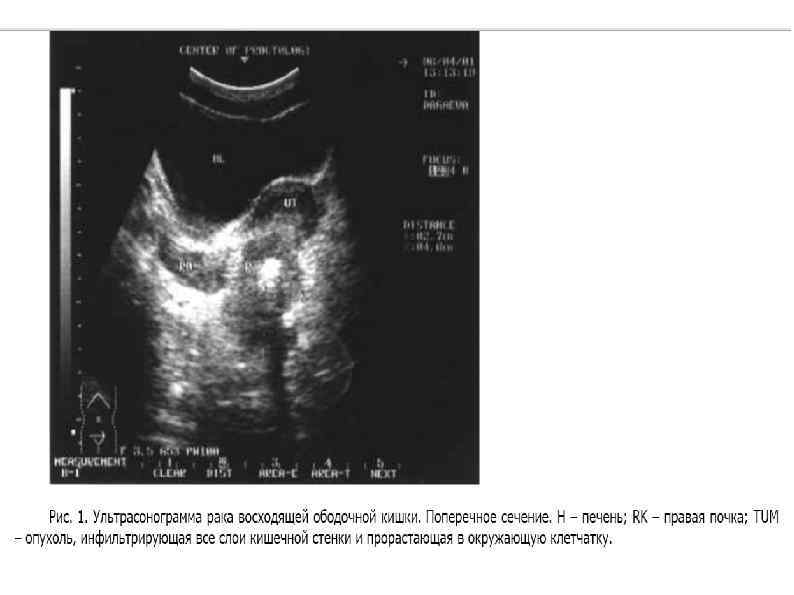

Объяснение: Токсико-анемическая форма Энтероколитическая форма Диспепсическая форма Обтурационная форма Псевдовоспалительная форма - на 1 Объяснение: Токсико-анемическая форма Энтероколитическая форма Диспепсическая форма Обтурационная форма Псевдовоспалительная форма - на 1 -е место выступают признаки воспалительного процесса в брюшной полости. Часто бывает проявлением течения РОК, осложненного гнойно-воспалительным процессом по типу параколита.

Объяснение: УЗИ в качестве скрининг-теста для выявления изменений в толстой кишке применять не рекомендуется: Объяснение: УЗИ в качестве скрининг-теста для выявления изменений в толстой кишке применять не рекомендуется: рак ободочной и прямой кишки с помощью исследования через переднюю брюшную стенку можно диагностировать только в том случае, если опухоль инфильтрирует кишку до мышечного слоя и занимает не менее 1/2 ее окружности.